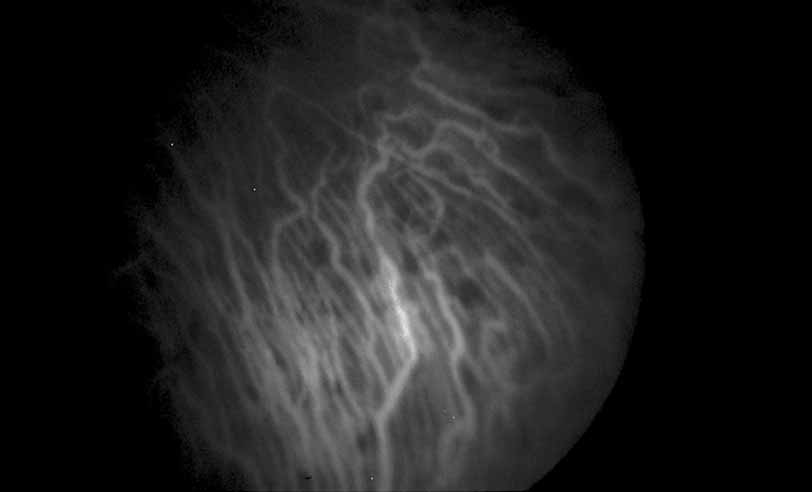

Fig. 28 Serpiginous choroiditis. ICG angiography early frame shows multiple hypofluorescent spots in the location of the lesions seen on color photography.

Fig. 29 Serpiginous choroiditis. ICG angiography later frame shows multiple hypofluorescent spots in the location of the lesions seen on color photography.